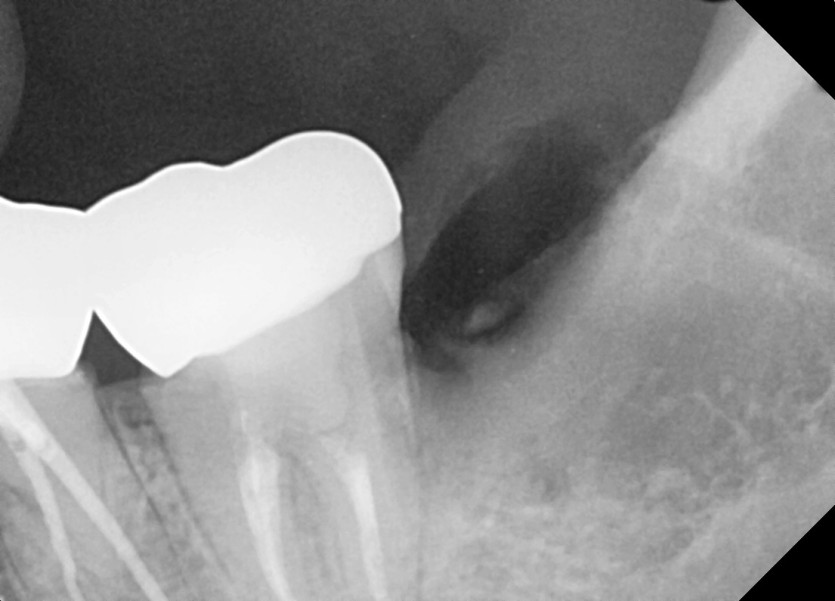

#38,48 사랑니 발치

구강 외과 전문의가 당일발치했습니다.